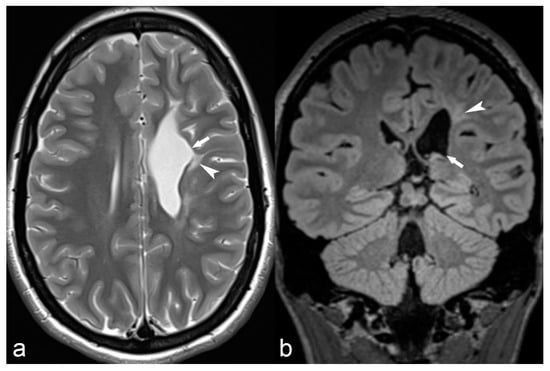

Rasmussen’s encephalitis is a rare syndrome of unknown etiology, probably immune-mediated, often presenting with drug-resistant epilepsy at childhood. MRI in Rasmussen’s encephalitis reveals progressive atrophy of one of the cerebral hemispheres (Figure 12), usually beginning in the opercular region [22]. Often, the cortex and subcortical white matter present hyperintense signal on T2WI and FLAIR [22].

Figure 12.

18-year-old female with medically refractory epilepsy. Coronal T2 (a) and FLAIR (b) images show hemispherical parenchymal volume loss and cortical thinning (asterisk) on the left side with resultant ex vacuo dilatation of the frontal (arrow) and temporal horns (arrowhead) of the left lateral ventricle, consistent with Rasmussen’s encephalitis.